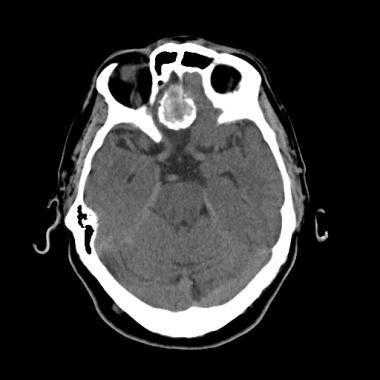

Менингиома лобной доли: КТ-картина. После введения контрастного вещества виден характерный вид «колеса со спицами» в структуре слабо контрастируемой опухоли. Несмотря на то, что данный паттерн чаще наблюдается при ангиографии, он также отмечается на томографических изображениях.

МРТ того же пациента, выполненная после предыдущей КТ: аксиальное Т1-взвешенное изображение после введения гадолиния и аксиальное Т2-взвешенное изображение. Видна крупная менингиома лобной области, расположенная срединно, со специфическим паттерном «колеса со спицами».

Псаммоматозная менингиома. КТ-исследование кальцифицированного объемного образования, обнаруженного на рентгеновском снимке. На томограмме, полученной на уровне верхней границы орбит, видна опухоль в области решетчатой пластинки (в области ольфакторной ямки).